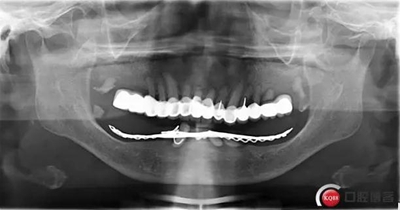

全過(guò)程約70日。因下牙槽骨較低,事前拍全景片。至今完成修復(fù)3個(gè)月,咀嚼效果良好。